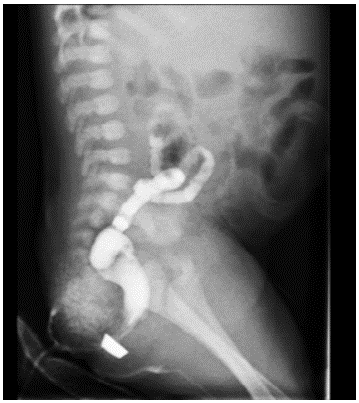

Colostomy was closed after 11 months, during which time instillations of saline solution were made through the rectum to stimulate the growth of the hypotrophic intestine. A barium enema was made before the procedure (Figure 4).

Barium enema is particularly useful to identify the anatomy and configuration of the colon, as well as the level of atresia and other abnormalities. 13 During the procedure, physicians should be very attentive of intraluminal pressure, as it may lead to perforation. 8 Therefore, in some cases, it can be performed only post-operatively, using a water-soluble contrast agent.